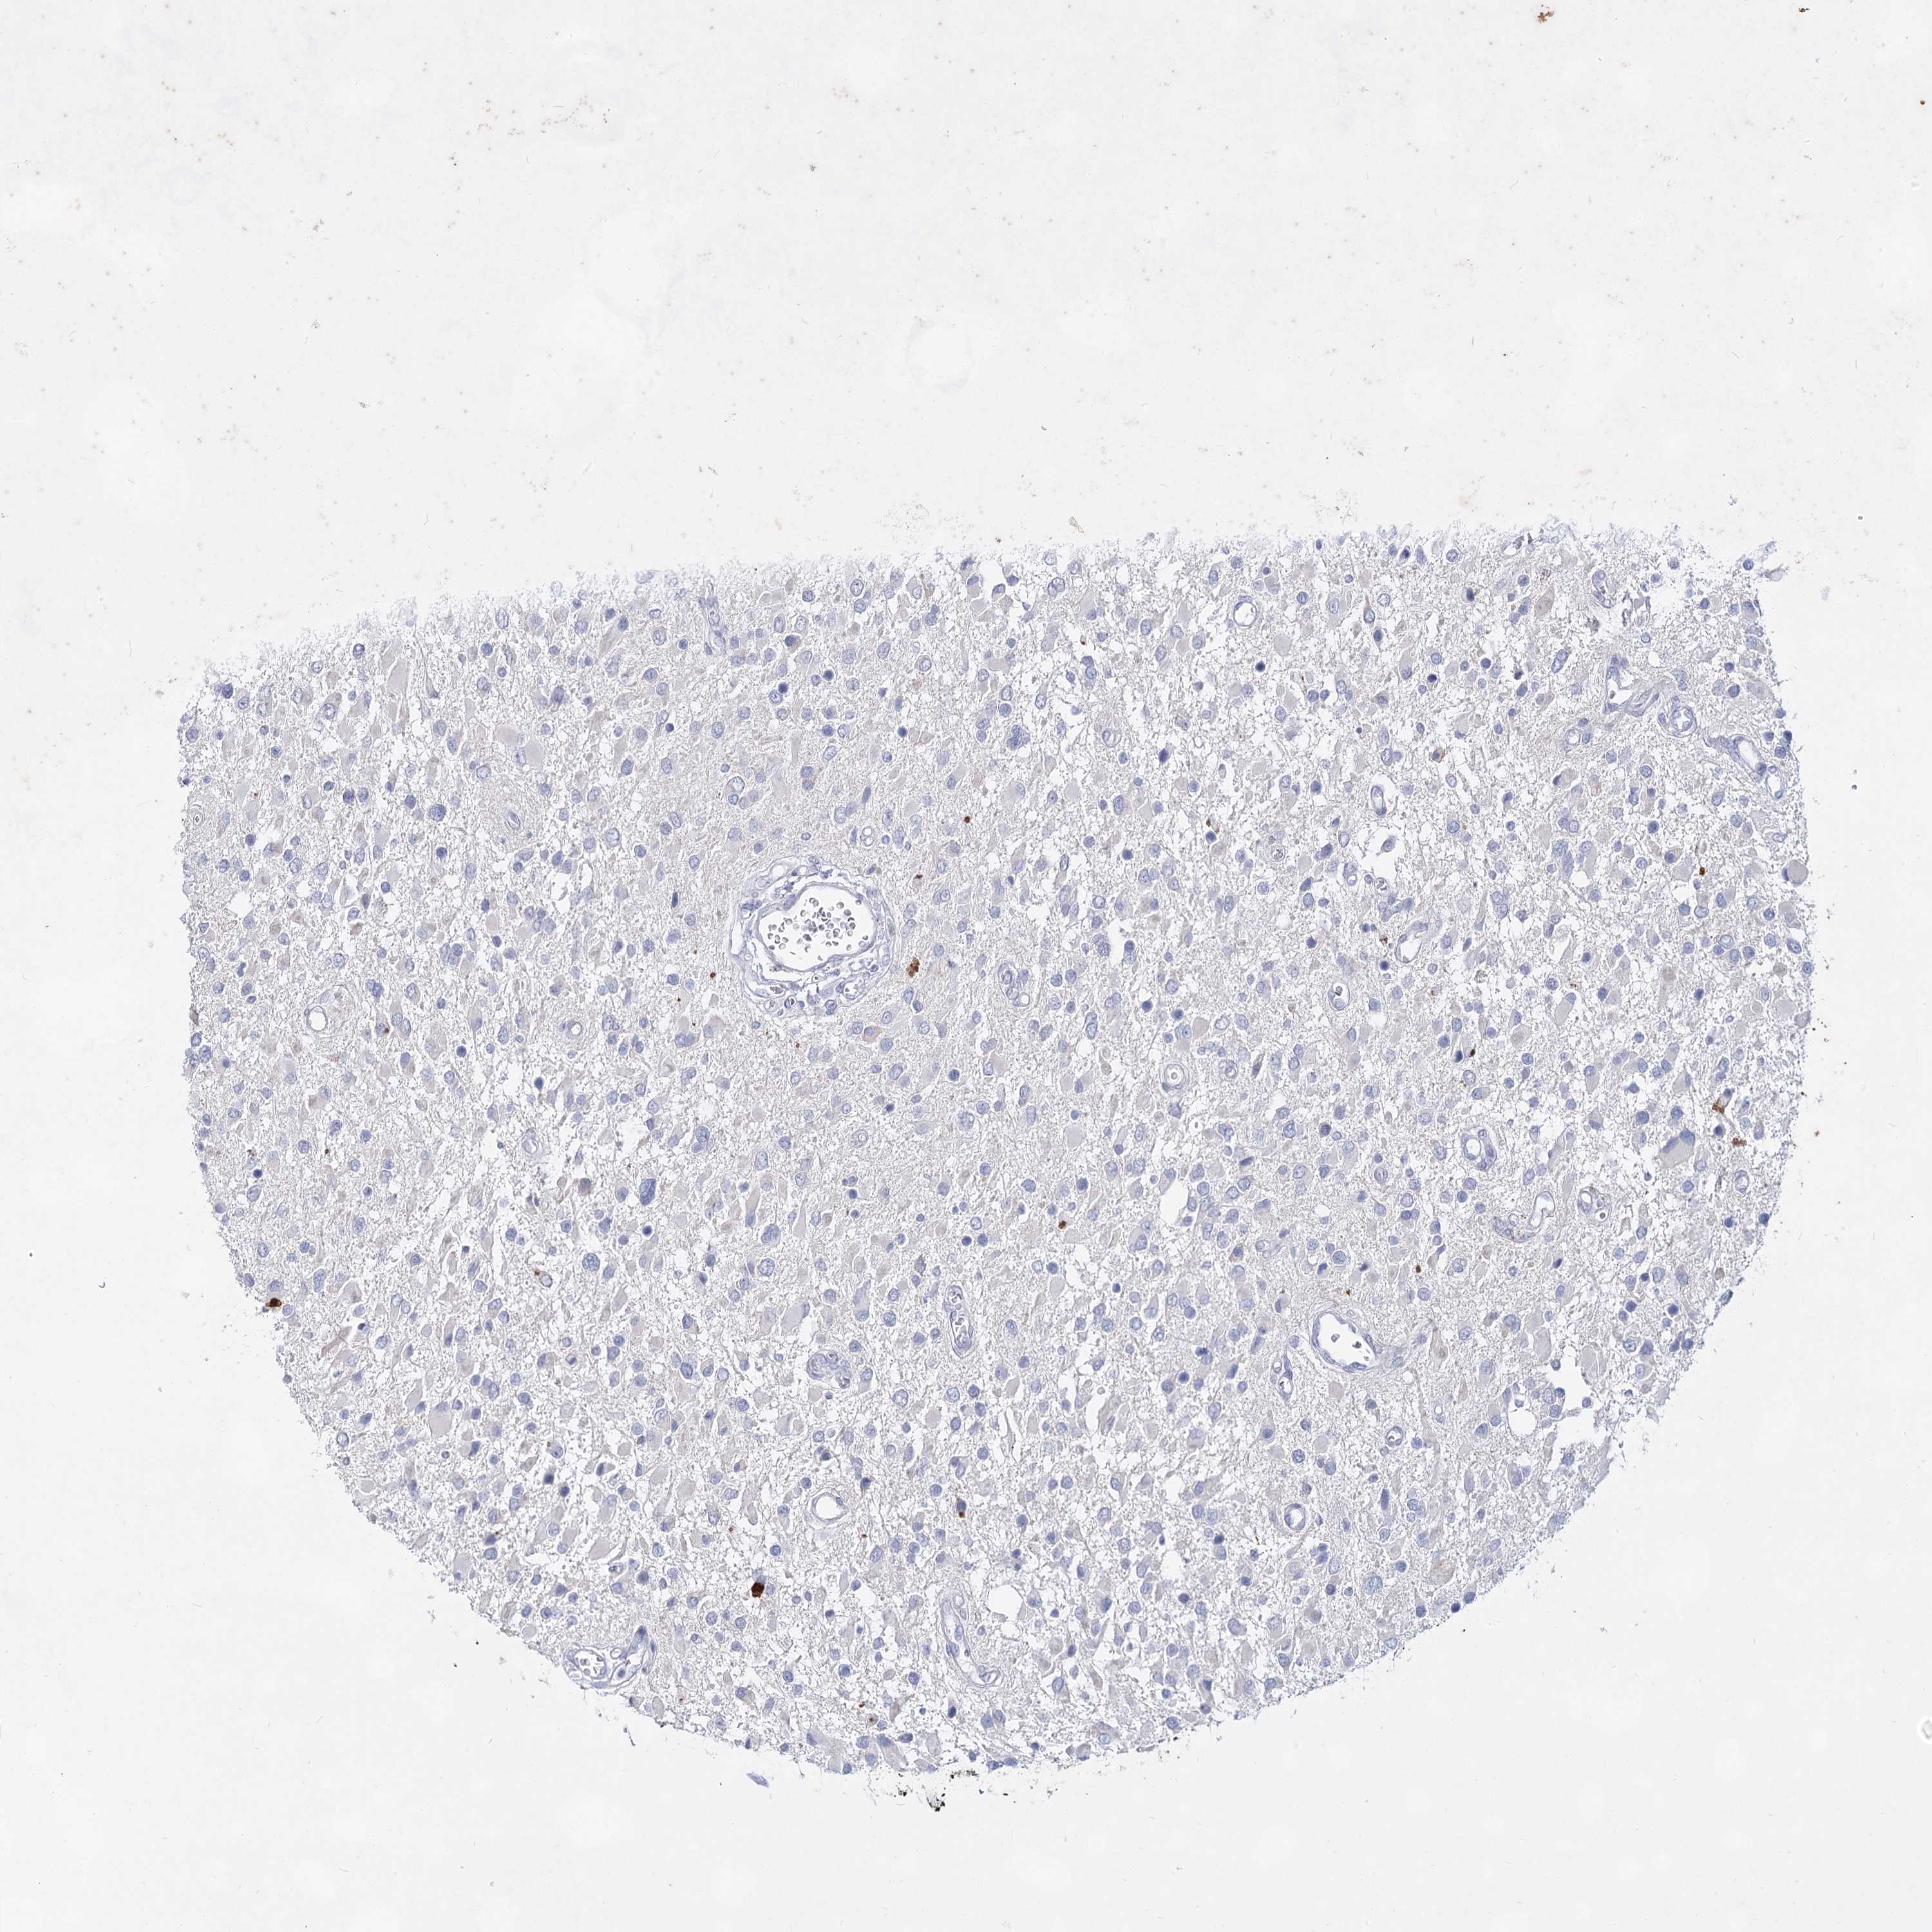

GLIOMA - Protein expressioni

A mouse-over function shows sample information and annotation data. Click on an image to view it in a full screen mode. Samples can be filtered based on level of antibody staining by selecting one or several of the following categories: high, medium, low and not detected. The assay and annotation is described here.

Note that samples used for immunohistochemistry by the Human Protein Atlas do not correspond to samples in the TCGA dataset.

Antibody stainingi

Antibody staining in the annotated cell types in the current human tissue is reported as not detected, low, medium, or high, based on conventional immunohistochemistry profiling in selected tissues. This score is based on the combination of the staining intensity and fraction of stained cells.

Each image is clickable and will lead to virtual microscopy that enables deeper exploration of all samples and also displays staining intensity scores, fraction scores and subcellular localization as well as patient and tissue information for each sample.

Antibody HPA038668

Antibody HPA038669

Staining

High

Medium

Low

Not detected

Intensity

Strong

Moderate

Weak

Negative

Quantity

>75%

75%-25%

<25%

None

Location

Nuclear

Cytoplasmic/membranous

Cytoplasmic/membranous,nuclear

Glioma, malignant, High grade

Glioma, malignant, Low grade

Glioblastoma, NOS